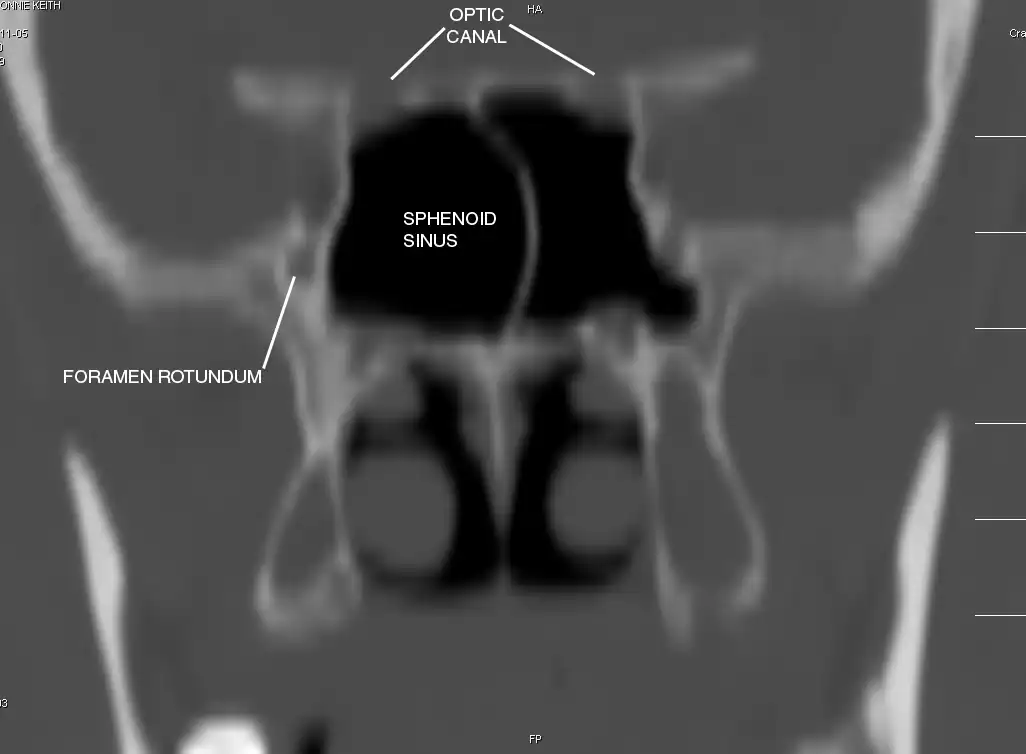

Sphenoid Sinus has 12 close structures: II, III, IV, V1, V2, VI, Vidian Nerve, Carotid artery, Brain, Dura, Pituitary.

- V2 = Maxillary division, Trigeminal Nerve: exits foramen rotundum, superomedial to V3's foramen ovale.

- C = Carotid Artery: often with bony dehiscence into sphenoid. Together with CN II forms opticocarotid recess.